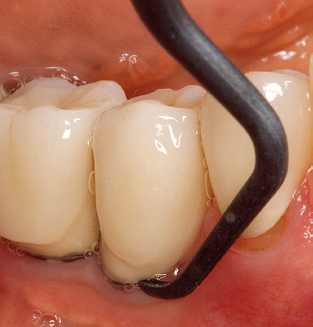

Good illumination of the working field facilitates the process considerably. The system used by the authors achieves this thanks to a 5x LED ring integrated in the handpiece. Naturally, a range of working tips for different indications is also offered. A straight, universally employable tip is the basic instrument required for machine cleaning of natural teeth (Fig. 5a and b). Curved tips, which allow access to exposed furcations, are also available for hard-to-reach areas in the posterior region (Fig. 6).